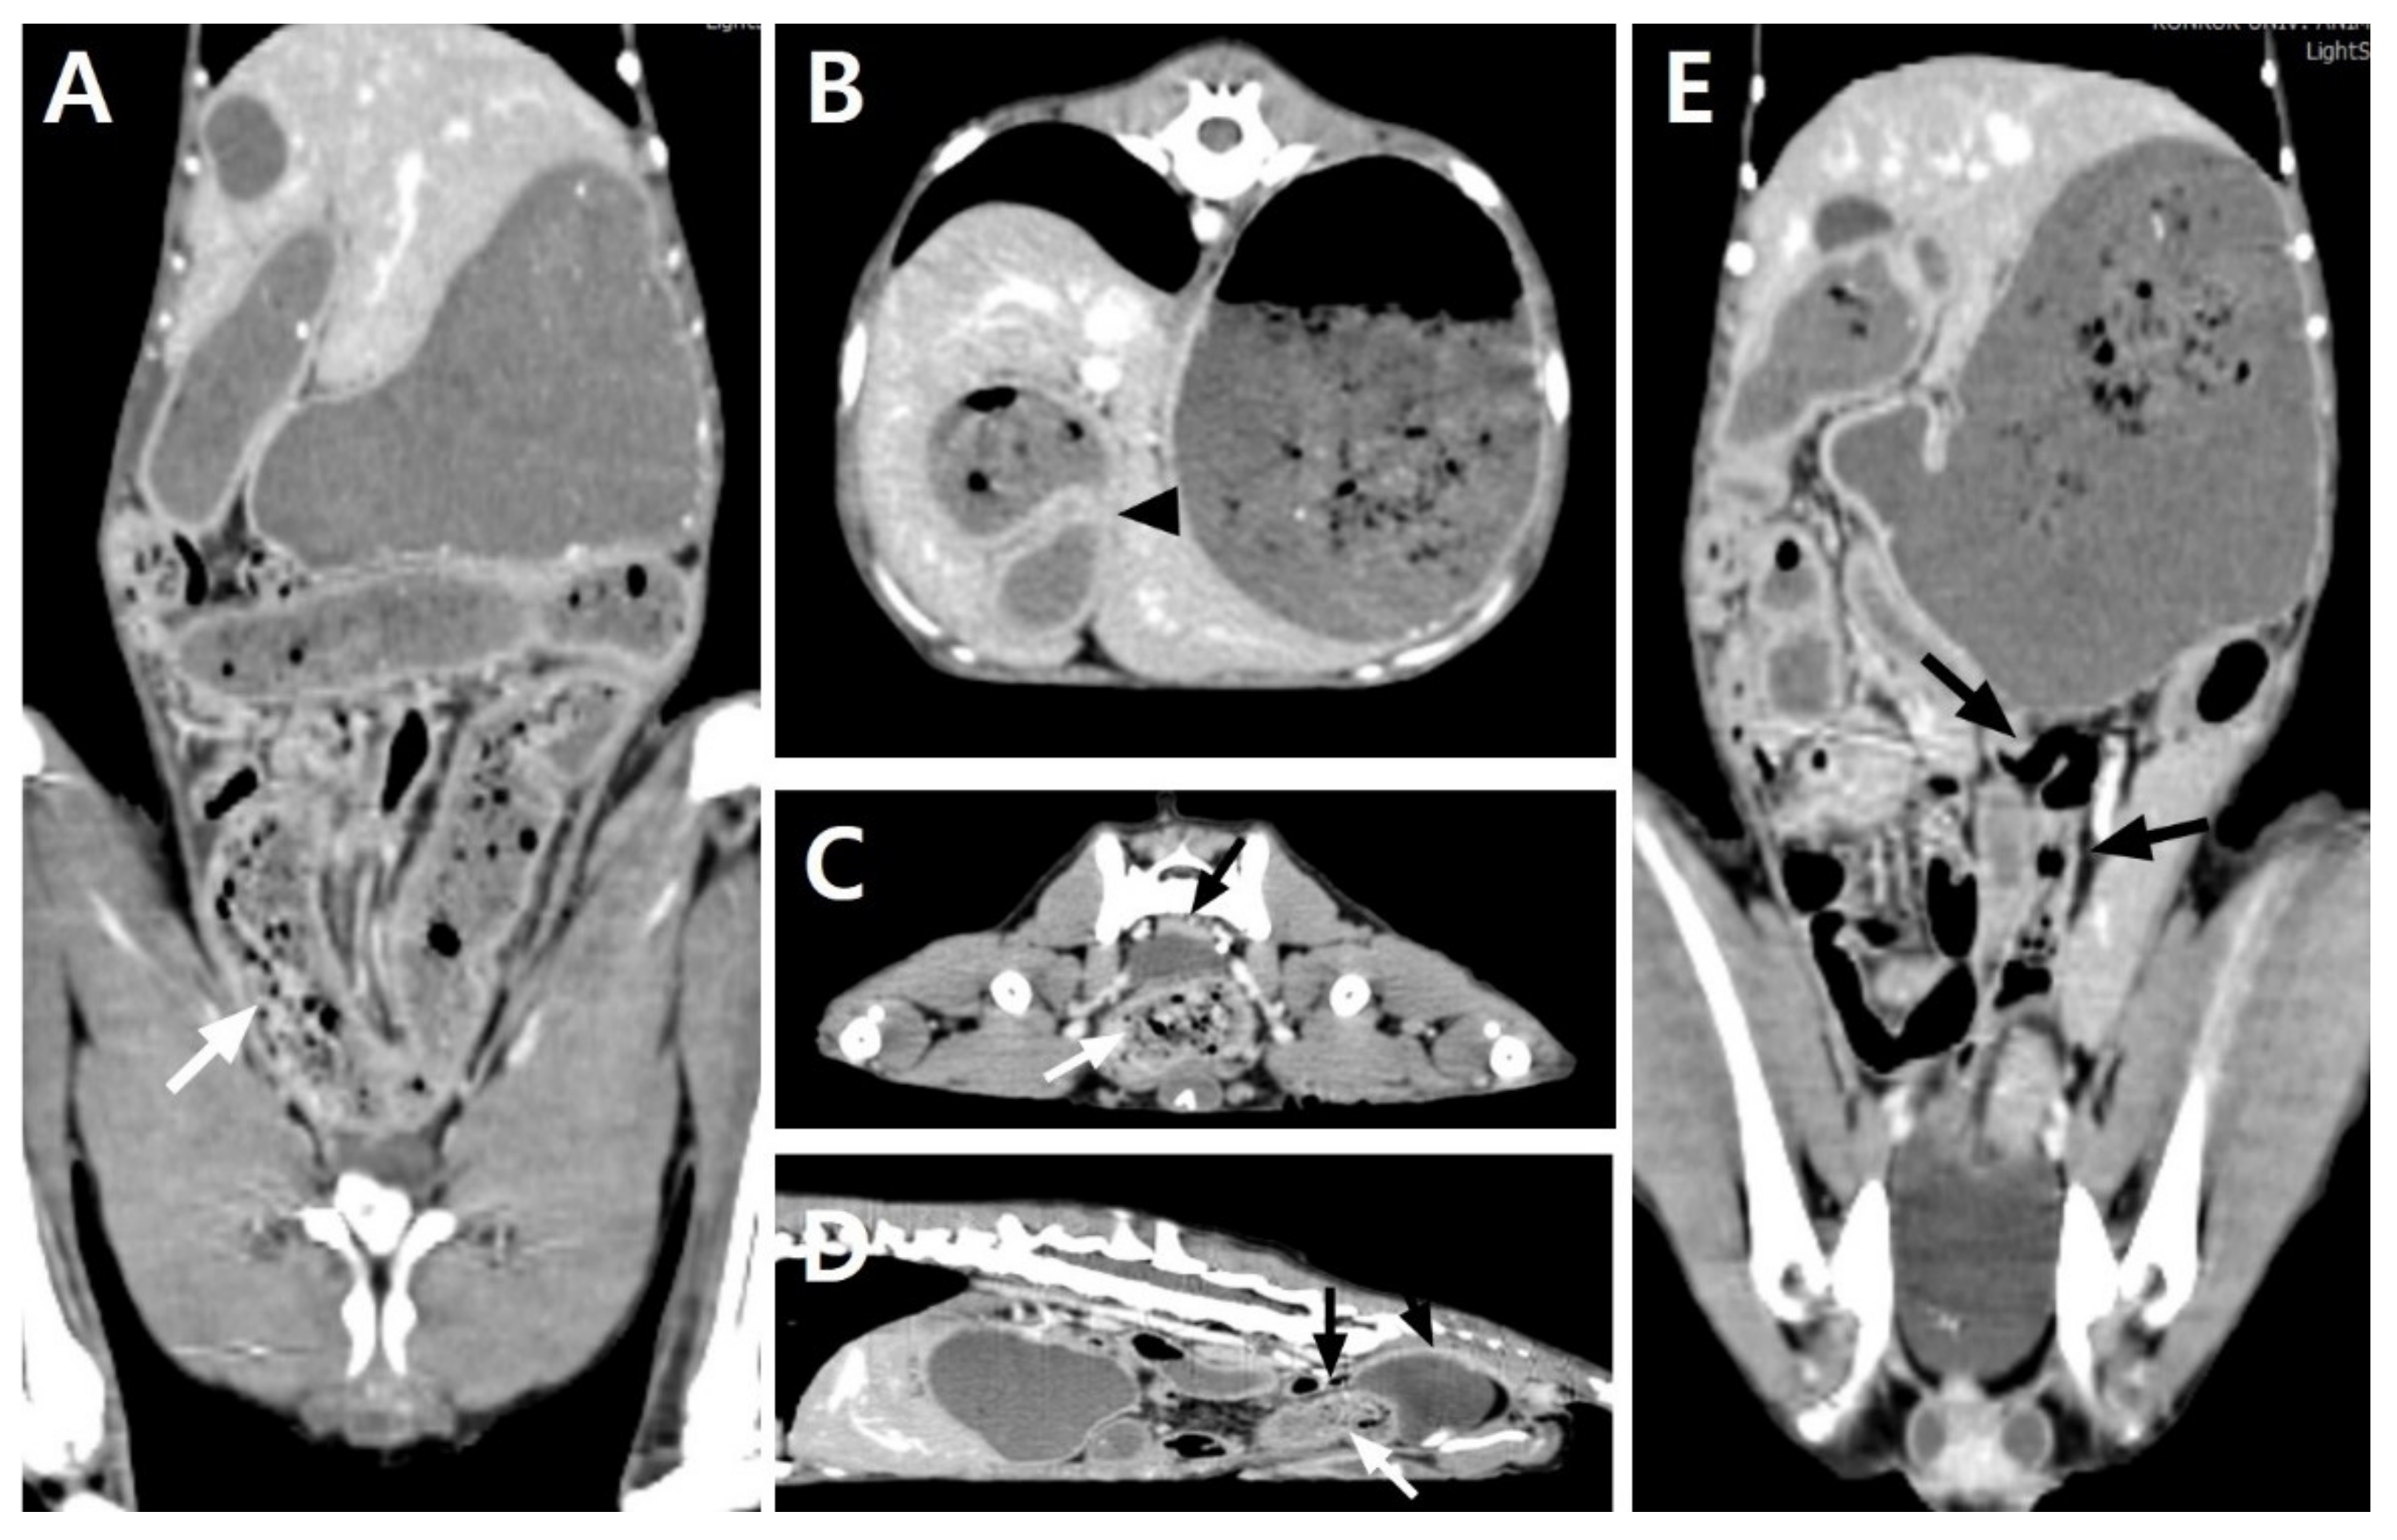

To identify and correct the cause of the SBO, an exploratory laparotomy was performed. The dog was premedicated with cefazolin (30 mg/kg intravenously (IV)), butorphanol (0.2 mg/kg IV), midazolam (0.1 mg/kg IV), and maropitant (1 mg/kg SC). General anesthesia was induced with propofol (4 mg/kg IV) and maintained with isoflurane in oxygen after endotracheal intubation. After an abdominal midline incision was made, diffuse fibrous adhesions were identified throughout the overall jejunum and between the jejunum and peritoneal wall. Bowel plication was identified between the proximal jejunums, adhering to the serosal layers with loops positioned at acute angles, causing the narrowing of the lumen. The jejunal loop proximal to the narrowed lesion was markedly distended and hyperemic, and the distal jejunum and ileum distal to the narrowed lesion were obstructed with hard intestinal contents that could not be squeezed (Figure 2A). The large intestines distal to the obstructed ileum were totally collapsed with no palpable contents. Adhesiolysis was performed using blunt dissection and electrotomy. After the adhesiolysis, a stenosed jejunal lesion was identified, with a fibrinous adhesive strand tightly encircling the narrowed jejunum, inducing a SBO (Figure 2B). The near-complete obstruction of the lesion led to a wide difference between the proximal and distal jejunal calibers with lack of luminal patency. The stenosed jejunum was removed and anastomosed using a previously described sutured anastomosis [10]. The resected intestinal segment was grossly inspected. The antimesenteric border was carefully incised to observe the adhesive stenosed lesion that caused the SBO, and a strong, thick, fibrous tissue that formed between the adjacent intestinal serosa was identified to markedly reduce the jejunal lumen (Figure 2C). No other obvious gross abnormalities were observed in the affected jejunum. By direct observation and palpation, it was confirmed that there were no pathological changes or impaired patency of the stomach or other intestinal segments. Cytology and bacterial culture using a small amount of abdominal effusion and adhesive peritoneum revealed no bacterial growth, but a histopathological analysis of the resected intestine was not performed because it was a financial burden to the owner.

The hardened fecal-like contents were removed via the enterotomies that were made over the distal end of the jejunum and ileum and were identified as hard and dry fecal matter corresponding to a fecal score of 1. The enteronotomy sites were closed with 3-0 polydioxanone (PDS) in a simple interrupted pattern. After securing the intestinal patency and confirming that there was no leakage, the serosal surfaces of the entire small intestine were closely examined, and a remarkable serosal injury of 7 cm in length was identified in the proximal jejunum where the adhesion was separated (Figure 3A). To prevent re-adhesion of the damaged serosa, an autologous peritoneal graft (APG) was transplanted to cover the entire damaged lesion. As an APG, 8 × 1.5 cm of the parietal peritoneum was harvested at the middle of the left-side of the abdomen (Figure 3B). The APG was expanded over the injured serosal surface and attached with several simple interrupted sutures using 3-0 PDS II (Ethicon, Somerville, NJ, USA; Figure 3C). The margin of the excised parietal peritoneum was apposed by a simple continuous suture using 4-0 PDS II (Ethicon). The abdomen was fully lavaged with warm saline and closed routinely.

Figure 2. Intraoperative photographs of a dog that presented with postoperative small-bowel obstruction with small-bowel fecal signs in computed tomography images. (A) The proximal jejuna were adhered, inducing plication at acute angles (white arrowheads); they were also markedly dilated and hyperemic. The distal jejunum and ileum were mildly dilatated and contained hard intestinal contents that could not be moved or crushed (black arrowheads). (B) After the release of the entrapped jejunal segments, a fibrinous adhesive strand was observed to have tightened the middle region of the jejunum, inducing jejunal stenosis (white arrow). A large discrepancy in the intestinal lumen was identified between the proximal and distal jejunum to the stenosed lesion. (C) Thick, fibrous adhesive tissue developed between the adjacent serosa and reduced the intestinal lumen (black arrows).

Figure 3. Intraoperative photographs representing the damaged serosal surface of the jejunum after adhesiolysis in a dog. (A) The proximal jejunum, which was released after adhesiolysis, represents the damaged serosal surface of approximately 7 cm in length (white arrows). (B) A parietal peritoneum (8 × 1.5 cm rectangular shape) was harvested from the left side of the abdominal wall. (C) The excised peritoneal graft was attached to the injured serosal surface with simple interrupted sutures to cover the entire damaged serosa.